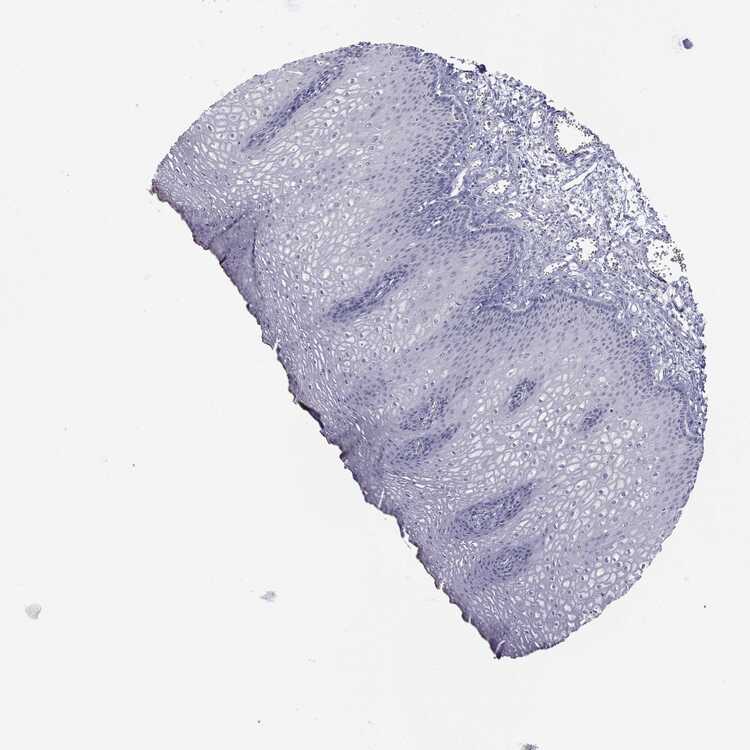

ESOPHAGUS - Antibody stainingi

Antibody staining in the annotated cell types in the current human tissue is reported as not detected, low, medium, or high, based on conventional immunohistochemistry profiling in selected tissues. This score is based on the combination of the staining intensity and fraction of stained cells.

Each image is clickable and will lead to virtual microscopy that enables deeper exploration of all samples and also displays staining intensity scores, fraction scores and subcellular localization as well as patient and tissue information for each sample.

Antibody HPA004179Antibody HPA007235Antibody HPA008855Antibody CAB000036Antibody CAB001986Antibody CAB080102Antibody CAB080103

Squamous epithelial cells HighLowLowMediumNot detectedNot detectedNot detected